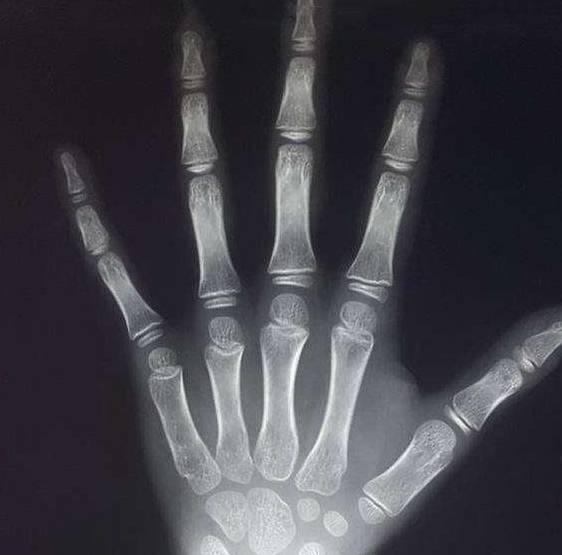

收集儿童身体部分的x光片

图中的第六根脚趾有独立,完整的骨骼结构,因此或许能提供一些行动上的